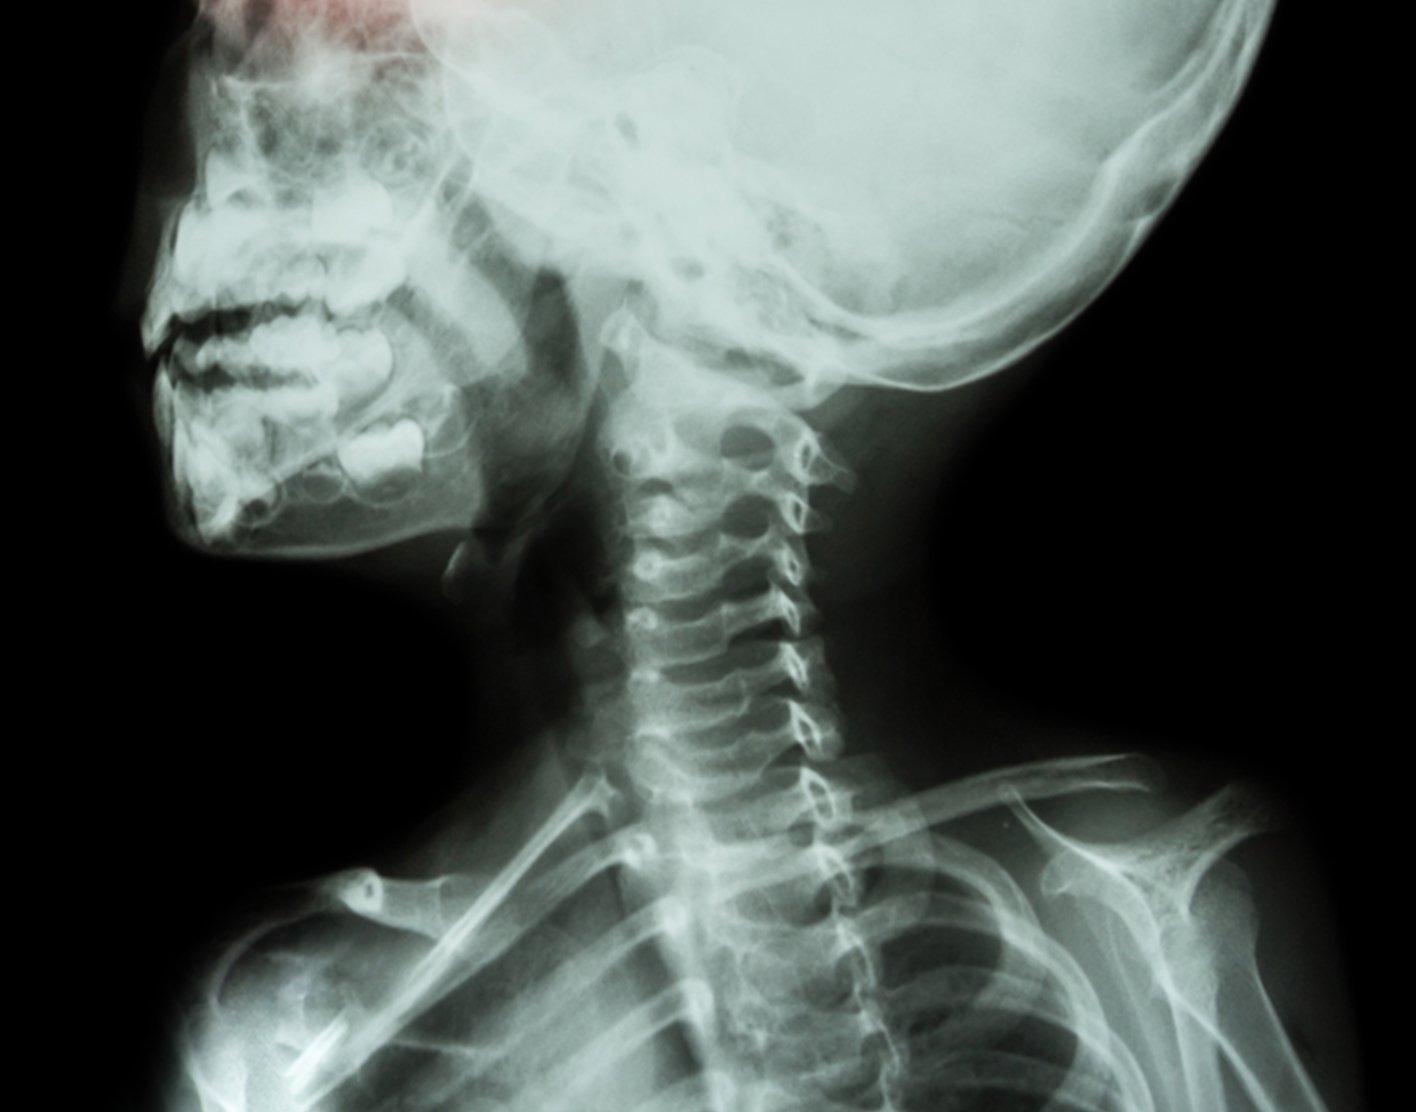

Neck x-ray

A neck x-ray is an imaging test to look at the cervical vertebrae. These are the 7 bones of the spine in the neck.

The x-ray is used to evaluate neck injuries and numbness, pain, or weakness that does not go away. A neck x-ray can also be used to help see if air passages are blocked by swelling in the neck or something stuck in the airway.

A neck x-ray can detect:

Breathing in a foreign object - Broken bone (fracture)

- Disk problems (disks are the cushion-like tissue that separate the vertebrae)

- Extra bone growths (bone spurs) on the neck bones (for example, due to osteoarthritis)

- Infection that causes swelling of the vocal cords (croup)

- Inflammation of the tissue that covers the windpipe (epiglottitis)

- Problem with the curve of the upper spine, such as

kyphosis - Spine joint that is out of position (dislocation)

- Thinning of the bone (

osteoporosis ) - Wearing away of the neck vertebrae or cartilage

- Abnormal development in the spine of a child